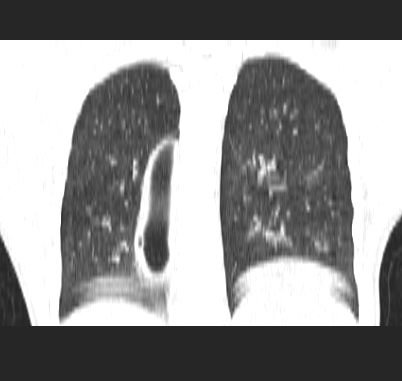

标题: CT19170:男 24岁,胸部外伤一周行CT检查 [打印本页]

男 24岁,胸部外伤一周行ct检查 未传纵隔窗

肺撕裂伤液气囊形成

肺撕裂伤液气囊形成.

支持首先考虑肺裂伤形成的液气囊肿。

考虑外伤引起的肺囊肿可能性大,